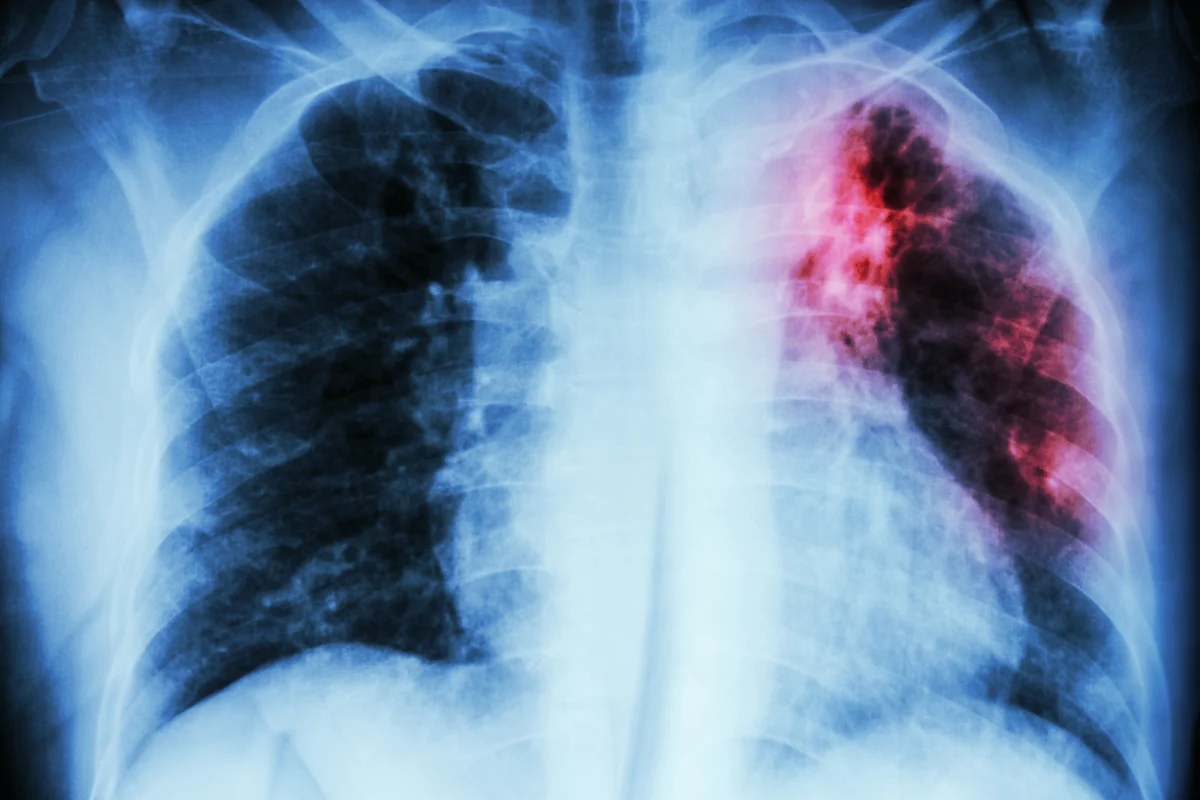

Security debates often centre on armies, weapons, and cyber defences, but a major threat to peace and stability spreads silently: infectious diseases. HIV, tuberculosis (TB), and malaria – exacerbated by underfunded health systems – cross borders, disrupt economies and endanger societies. This is not just a health issue but a direct threat to national and global security. Underfunding health leaves nations defenceless against one of the most dangerous enemies of our time. Tuberculosis is one of the diseases the UK can’t afford to ignore. In England, rates of TB rose by 11 per cent in 2023 – the largest increase since national reporting began in 2000. This is especially concerning given that the spread of multidrug-resistant TB globally poses a major health security threat. This form of the disease is caused by bacteria which are resistant to at least two of the most effective anti-TB drugs. It is hard to treat, increases costs for health systems already under strain, and has high mortality rates. Antimicrobial Resistance caused 1.27 million deaths in 2019, one in three of these were due to drug-resistant TB. If left unchecked, TB and drug-resistant TB could spread globally and kill millions more. For the UK, tackling infectious diseases like TB is not an act of generosity; it’s a matter of national interest. Cutting health funding amid rising conflict and humanitarian need would be a strategic mistake, weakening both our global standing and our domestic resilience. Investment in science and innovation – new vaccines, diagnostics, and treatments – is vital for global health security and for strengthening international partnerships and diplomacy. The UK has been a leading funder of global health research and development, particularly for neglected diseases like malaria, HIV, and TB. From 1994 to 2022, UK-supported product development is projected to save 1.43 million lives and prevent 183 million disease cases. That is why it is so vital that the UK maintains its leadership at the upcoming replenishment for the Global Fund to Fight AIDS, Tuberculosis and Malaria next month. Since its creation in 2002, the Global Fund has become one of the world’s most effective health security investments, saving 70 million lives worldwide, strengthening health systems, and supporting pandemic prevention efforts. As Chair of the All-Party Parliamentary Group on Global Tuberculosis, I have seen first-hand how these investments translate into tangible benefits for people both overseas and here in the UK. Every pound invested saves lives, protects people in this country, safeguards the NHS from the burden of untreatable infections, and strengthens Britain’s defences against future outbreaks. In Ethiopia, the Fund has helped to train 40,000 community health workers who deliver preventive, maternal and child health services – including early detection and treatment for HIV, malaria and TB – directly in people’s homes. This type of initiative has resulted in incidence of TB, malaria, and HIV falling by 42 per cent in the countries where the Global Fund invests since 2002, and deaths falling by 63%. When conflict disrupted infrastructure and displaced millions in Ukraine, the Fund helped maintain essential health services — supporting mobile clinics, supplying testing equipment, and providing power generators to regional laboratories. These efforts have ensured that people continue to receive life-saving treatment for HIV and TB, preventing new outbreaks and preserving hard-won progress. This is not simply humanitarian assistance; it is a practical contribution to European stability and to the UK’s own health security. That’s why I believe investing in global disease prevention is firmly in my constituents’ best interest. Global health security is national security. The time to act is now. Sojan Joseph is the chair of the All-Party Parliamentary Group on Global Tuberculosis and Labour MP for Ashford This article has been produced as part of The Independent’s Rethinking Global Aid project